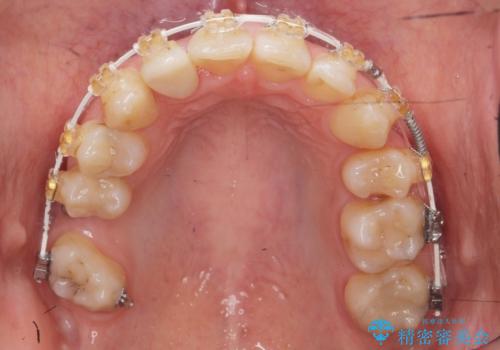

左下の親知らず、左上の小臼歯が残根状態で一本抜いたほかは抜かずに矯正しました。

①保存不可能な歯は抜歯しそのすき間を矯正で閉じる

②右上の親知らずは活かしてブリッジの支台にする

という、予算がかからないように歯を保存する治療計画を立てました。

予算的に右下の一番奥のインプラントは難しかったため、できる限り対応しました。